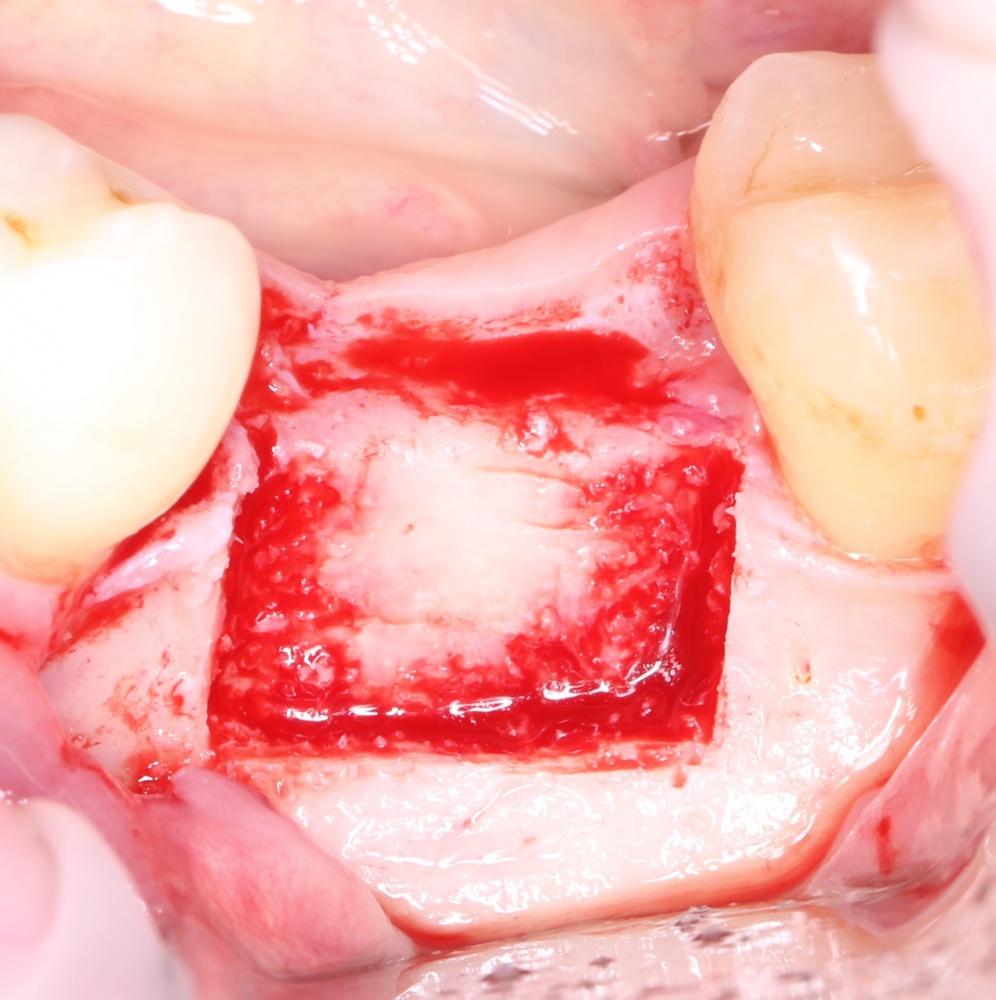

Кстати, обрати внимание на ширину альвеолярного гребня (левая картинка). Она чуть меньше 3 мм. Это объясняет, почему я засомневался в возможности установки имплантатов одновременно с остеопластикой. Понятно и без КЛКТ.

Возвращаемся к основной операционной области. Еще раз посмотрим на альвеолярный гребень, поофигеваем от его ширины и моих грандиозных планов: